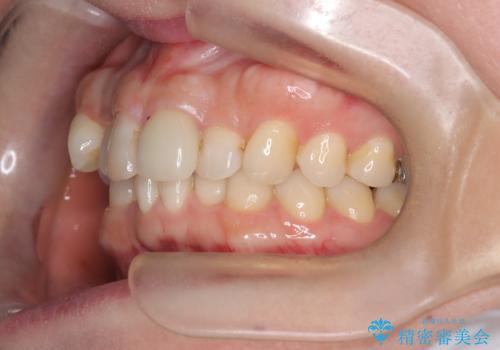

八重歯と口元のバランスを整えた矯正治療

- 「八重歯をきれいにしたい」とのご希望で来院されました。診察の結果、上顎犬歯の萌出スペースが不足しており、典型的な八重歯(叢生)の状態でした。上下の歯の中心(正中)のずれや、奥歯のかみ合わせ(臼歯関係)のアンバランスも見られたため、単に見た目を整えるだけでなく、全体的な機能改善も必要と診断しました。

治療中は咬合バランスや歯列の中心(正中)の位置にも注意を払い、最終的には上下の正中が一致し、左右の臼歯関係も理想的な形に改善されました。見た目の変化はもちろん、かみ合わせの安定や清掃のしやすさも向上。

患者さんからは「笑ったときの印象が大きく変わって嬉しい」「しっかり噛めるようになった」との感想をいただきました。現在は保定装置で後戻りを防ぎながら、良好な状態を維持しています。